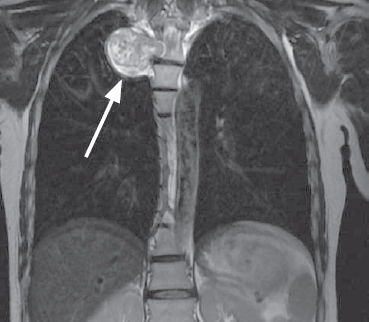

Паравертебральные опухоли медиастинальной локализации — обширная группа патологических процессов с различной гистологической картиной и биологическим поведением, хирургическим лечением при которой занимаются врачи разных специальностей, таких как нейрохирурги и хирурги-онкологи. В настоящее время наиболее предпочтительным методом хирургического лечения данных объемных образований принято считать торакоскопическое удаление, ввиду наименьшей травматичности, меньшего количества осложнений и сокращения времени послеоперационного восстановления пациентов. Представлен клинический случай хирургического лечения пациентки с гигантской паравертебральной опухолью, исходящей из IV грудного корешка. Опухоль стала случайной находкой при выполнении плановой флюорографии. Очаговой неврологической симптоматики не отмечалось. Учитывая топографо-анатомические особенности объемного образования, пациентке было проведено комбинированное двуэтапное оперативное вмешательство: сначала выполняли ламинэктомию и удаление фораминального компонента опухоли из заднего доступа, затем одно портовое видеоассистированное торакоскопическое удаление медиастинально расположенного фрагмента опухоли. Операция проходила в условиях коллабированного легкого на стороне вмешательства. В послеоперационном периоде неврологического дефицита не отмечено, по данным контрольной интроскопии опухоль удалена тотально. По результатам гистологического исследования — нейрофиброма (Grade I). Приведенный клинический пример показывает успешную коллаборацию спинальных и торакальных хирургов, а также иллюстрирует возможности современной минимально инвазивной хирургии.